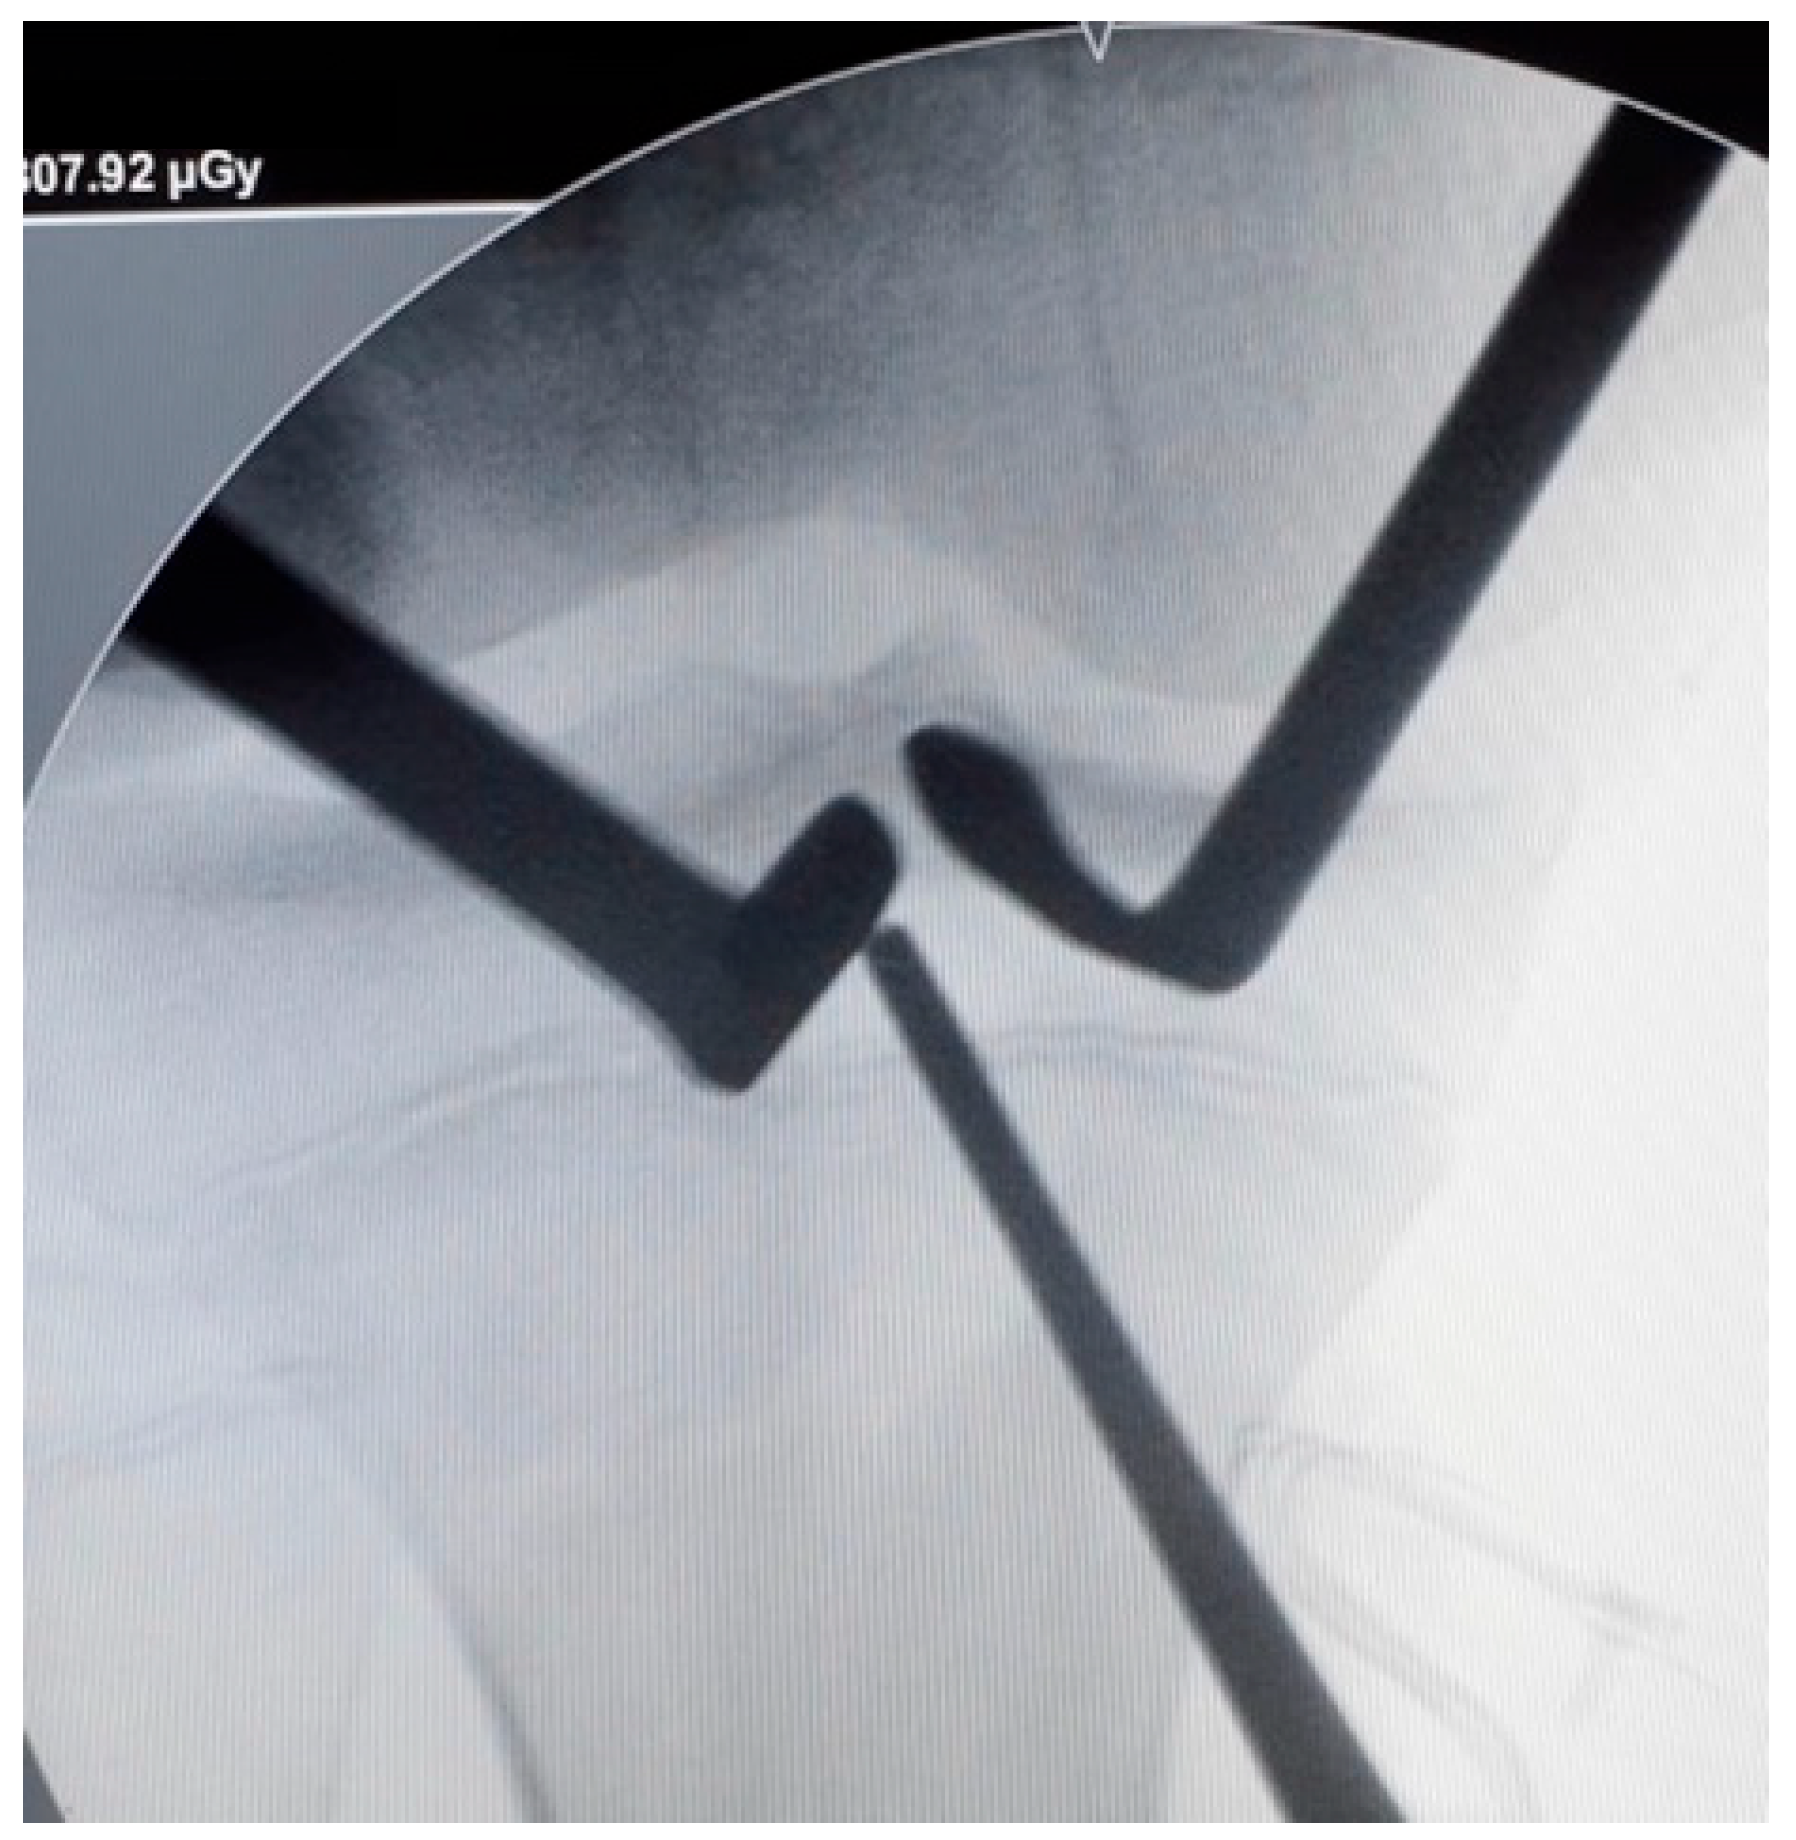

The tibial guide was then centered over the ACL tibial footprint under arthroscopic vision and an image intensifier (Figure 3). A guide pin was inserted proximal to the tibial physis and drilled in an outside-in direction. The angulation of the tibial guide varied depending on the position of the physis. The size of the tunnel was determined by the diameter of the double-bundle graft.

Figure 3.

Tibial tunnel positioning. The tibial tunnel is performed under radiological control. A guide-pin is inserted proximal to the tibial physis (right knee).